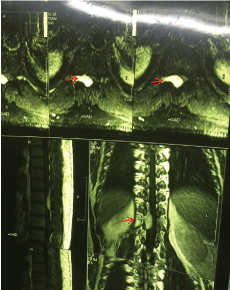

Extradural cavernous hemangiomas are usually isointense on T1W (Figure 1) and hyperintense on T2W images (Figure 2) and show homogenous contrast enhancement (Figure 3) because of the presence of sinusoidal channels.

Figure 1: Sagittal T1-weighted image shows an iso signal extra-medullary extra-dural soft tissue mass in right side of the dorsal spinal canal at T11 & T12 vertebral levels, causing thecal sac compression.

Figure 2: Sagittal T2-weighted image showing high signal intensity in the mass lesion.

Figure 3: Axial (superior) sagittal (left) and coronal post-contrast, T1-weighted images show intense homogenous enhancement of the epidural lesion with moderate extension into the right foramina (red arrow).